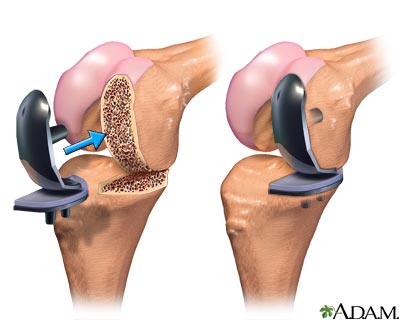

Partial knee replacement surgery removes damaged tissue and bone in the knee joint. It is done when arthritis is affecting primarily only one part of the knee. The areas are replaced with an artificial implant, called a prosthetic. The rest of your knee is preserved. Partial knee replacements are most often done with smaller incisions, so there is less recovery time.

- The damaged bone and tissue are removed.

- A part made from plastic and metal is placed into the knee.

- Once the part is in the proper place, it is attached with bone cement or fixated to the bone.